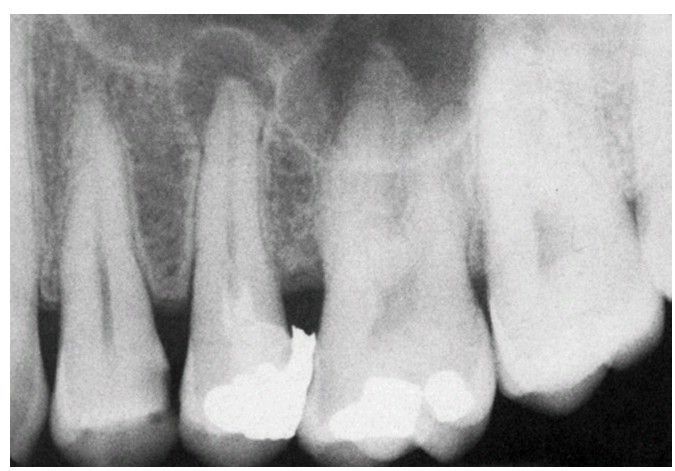

Granuloma of second premolar

. The surgeon should not curette periapically around this second premolar to remove granuloma because the risk for sinus perforation is high.